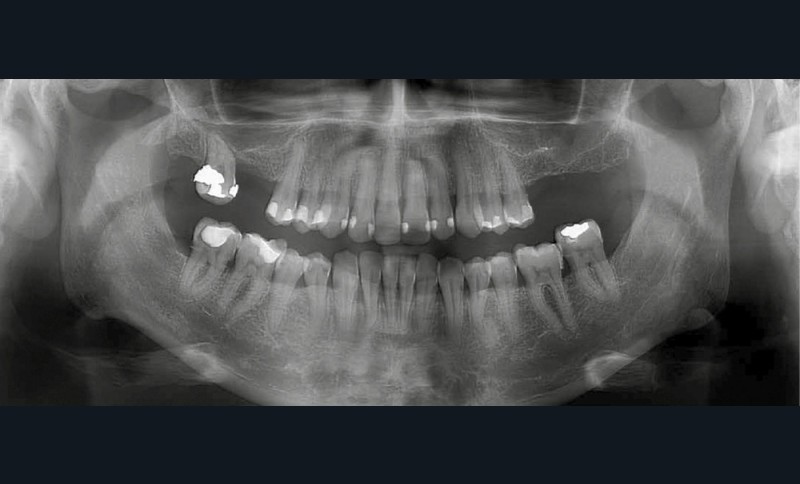

L’importance de la réhabilitation des secteurs postérieurs est démontrée notamment par la rotation de la 17 et l’égression de la 37. Ces étapes seront vues dans un second temps. Les étapes de traitement acceptées, nous pouvons établir un plan de rendez-vous (fig. 3).